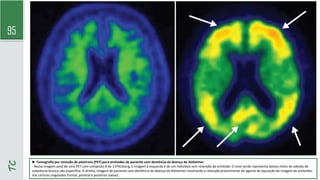

TC

► Tomografia por emissão de pósitrons (PET) para amiloides de paciente com demência da doença de Alzheimer.

- Nessa imagem axial de uma PET com composto B de 11Pittsburg, a imagem à esquerda é de um indivíduo sem retenção de amiloide. O sinal verde representa baixos níveis de adesão de

substância branca não específica. À direita, imagem de paciente com demência da doença de Alzheimer mostrando a retenção proeminente do agente de aquisição de imagem de amiloides

nos córtices cingulados frontal, parietal e posterior (setas).